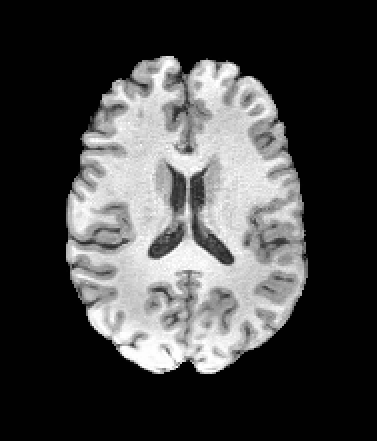

A distinctive strength of MetaVoxel is its ability to perform flexible zero-shot inference for a broad spectrum of tasks with arbitrary subsets of inputs. To enable this, we reinterpret the RePaint strategy described in Section 2: just as RePaint performs conditional image generation by specifying a binary mask that marks which pixels are fixed, we can further designate any subset of MetaVoxel’s variables as “known” conditions. At each denoising step, these known variables are overwritten with their re-noised values, ensuring that they remain fixed throughout the sampling trajectory, while the remaining variables evolve according to the learned reverse process. This keeps the synthesized variables consistent with the conditioning, analogous to how RePaint produces inpainted regions consistent with the known region. Although MetaVoxel learns the joint distribution , different downstream tasks can be realized simply by choosing which variables to fix during sampling. Image inpainting is achieved by fixing pixel regions of the image variable***see examples in Appendix (Figure B.2); conditional image generation by fixing variables such as age or sex; regression tasks (e.g., age estimation) by fixing any combination of image and sex; and classification tasks (e.g., sex prediction) by fixing any combination of image and age. As more variables are included in the joint model, the range of possible zero-shot tasks naturally expands. For example, when multiple imaging modalities are present, fixing one modality and sampling the other enables image-to-image translation.

| Input | Inpainting with Left Half of the Image Fixed | ||||

|---|---|---|---|---|---|

![]() |

|